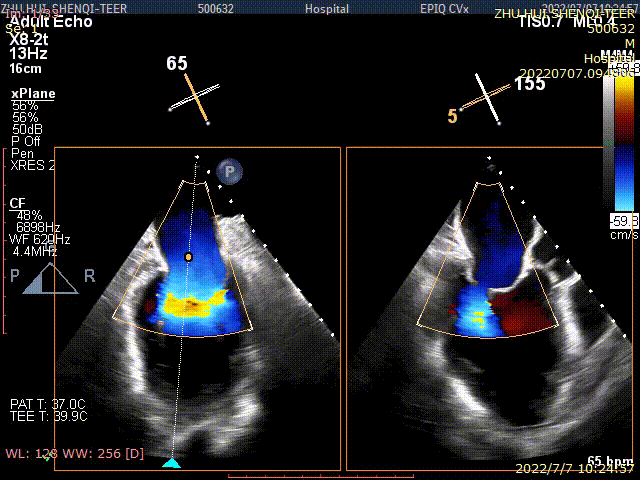

术后TEE显示,二尖瓣双孔化形成,反流明显减少